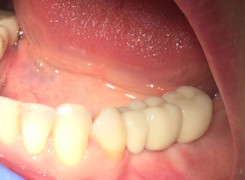

Pan Ryszard trafił do Naszego Gabinetu z jasno sprecyzowanym oczekiwaniem. Miał 84 lata i chciał odzyskać możliwość swobodnego spożywania posiłków oraz poprawienia sobie komfortu życia a także prosił aby przywrócić mu piękny uśmiech jakim cieszył się przed laty. Już na początku pierwszej rozmowy zastrzegł, że interesuje go wyłączenie rozwiązanie uzupełnieniem protetycznym stałym. Nie miał zamiaru użytkować żadnych protez ruchomych. Mając na uwadze powyższe wykonaliśmy Panu Ryszardowi zdjęcie pantomograficzne oraz badanie tomograficzne szczęki i żuchwy na postawie których zapanowywaliśmy Pacjentowi optymalne rozwiązanie – stałe uzupełnienie protetyczne w postaci 28 koron cyrkonowych zamontowanych do dwóch belek cyrkonowych które będą przymocowane do 16 implantów w konfiguracji 8 wszczepów w szczęcie 8 w żuchwie. Po omówieniu powyższego planu przystąpiliśmy do Wspólnej pracy której efekty w poszczególnych etapach prezentujemy poniżej.